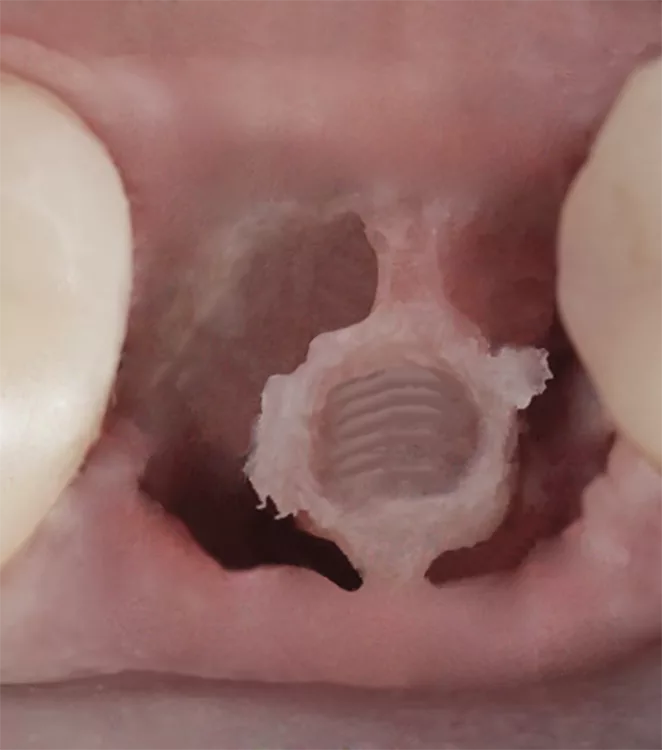

MIMI beschreibt die minimalinvasive Vorgehensweise in der Implantatchirurgie mit Hilfe der lappenlosen („flapless“) Champions-Implants-Navigation sowie der Möglichkeit der ossären Metamorphose (OMM) im weichen Knochen. Indem man beim biologisch orientierten MIMI-Verfahren lappenlos vorgeht, wird die den Knochen nährende Knochenhaut (Periost) maximal geschützt. Da ein Implantat verwendet wird, das gleichzeitig Gingivaformer, die definitive Halteschraube und den Abdruckpfosten (alles zusammen Shuttle genannt) umfasst, ist die Knochenfreilegung unter Anästhesie und somit eine zweite aktive OP obsolet. Idealerweise schließt der Shuttle äquigingival ab, sodass das (R)Evolution-Implantat ca. 1,5 mm subkrestal platziert werden kann. Liegt lediglich ein Restknochenbestand von 3 mm vor, wird die ganze Länge des Microgewindes ausgenutzt und auf Bone-Level inseriert.

Im harten Knochen D1/D2 erfolgt bei MIMI eine sogenannte krestale Entlastung, d.h., dass krestal die Kortikalis um 0,5 mm erweitert wird, um Druck auf die kortikale Knochenstruktur zu vermeiden. Bei einem Implantat von 3,5 mm Durchmesser erfolgt demnach die finale Bohrung mit 4,0 mm Ø, bei einem Implantat von 4,0 mm Ø (Einzelmolaren-Implantat) entsprechend mit einem Durchmesser von 4,5 mm usw. (Abb. 2).

Dr. Katrin Meyer und Champions-ImplantsIm weichen Knochen D3/D4, bei der horizontalen Distraktion schmaler Knochen (MIMIII), bei internen, direkten Sinusliften (IDS) und bei allen Sofortimplantationen (Extraktion und Implantation in nur einer Sitzung) kommen die patentierten Winkelstücke, die sogenannten WS-Condenser, zum Einsatz: Hierbei wird die spongiöse Knochenstruktur schonend verdichtet. In wenigen Minuten lässt sich damit aus einem D3/D4-Knochen ein optimaler D2-Knochen generieren.